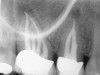

Figure 4a  Tooth No. 30 Nonsurgical root canal treatment had been completed 5 years before. The periapical radiograph revealed periradicular radiolucencies (periapical and in the furcation area).

Figure 4a